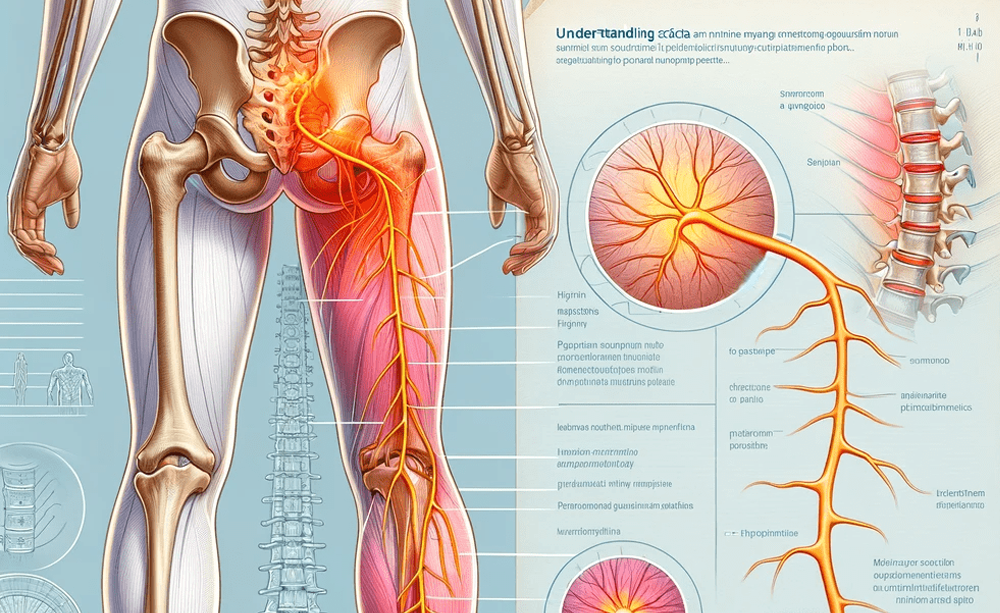

Sciatica

Back & Neck Disc